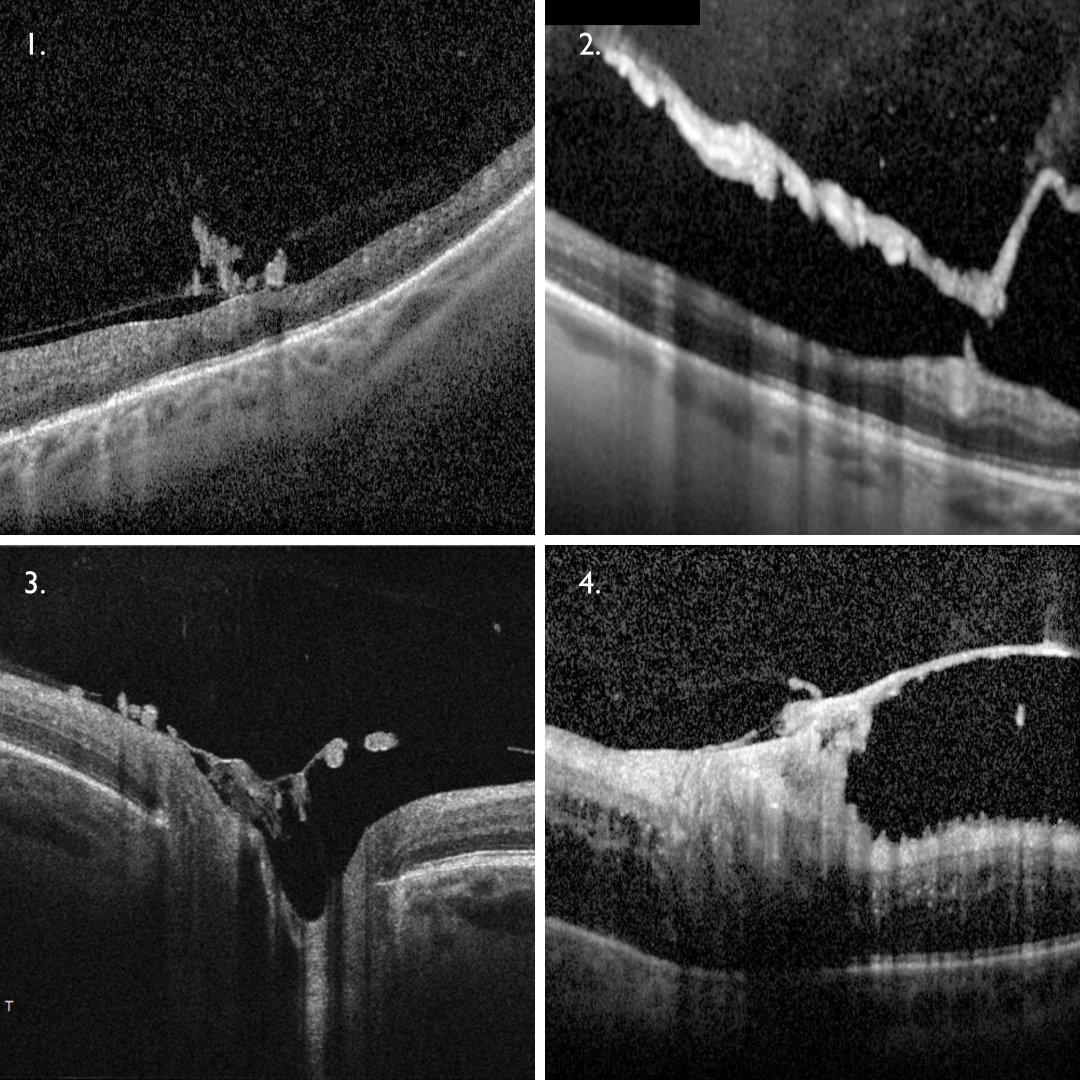

NVE presents on OCT as either hyper-reflective homogenous loops on the retinal surface that show posterior shadowing (1), or areas of hyper-reflectivity on the posterior hyaloid interface (2). OCT-A can confirm the presence of fine, irregular vessels within the vitreoretinal interface.

NVD appears as hyperreflective material sitting on optic disc surface and/or protruding into the vitreous (3). More advanced NVD can appear as a fibrovascular tissue overlying the disc with associated traction (4). OCT-A can confirm the presence of an irregular network of vessels above the optic disc surface.